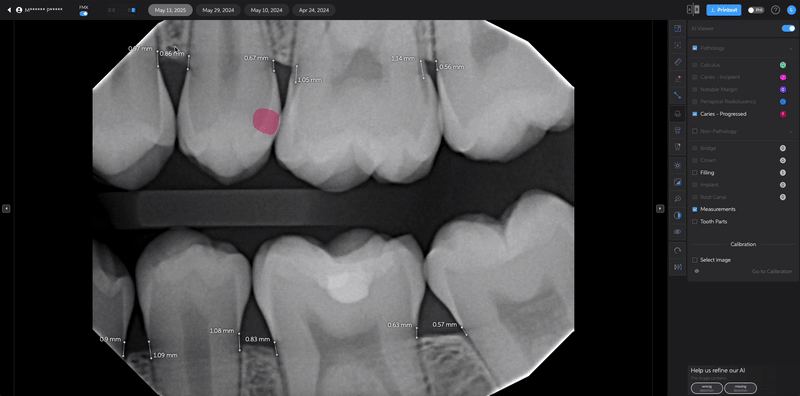

- Hover over the pathology you want to remove.

- Click the eye icon to hide the detection from view.

Useful when the AI highlights an area that does not require clinical attention.